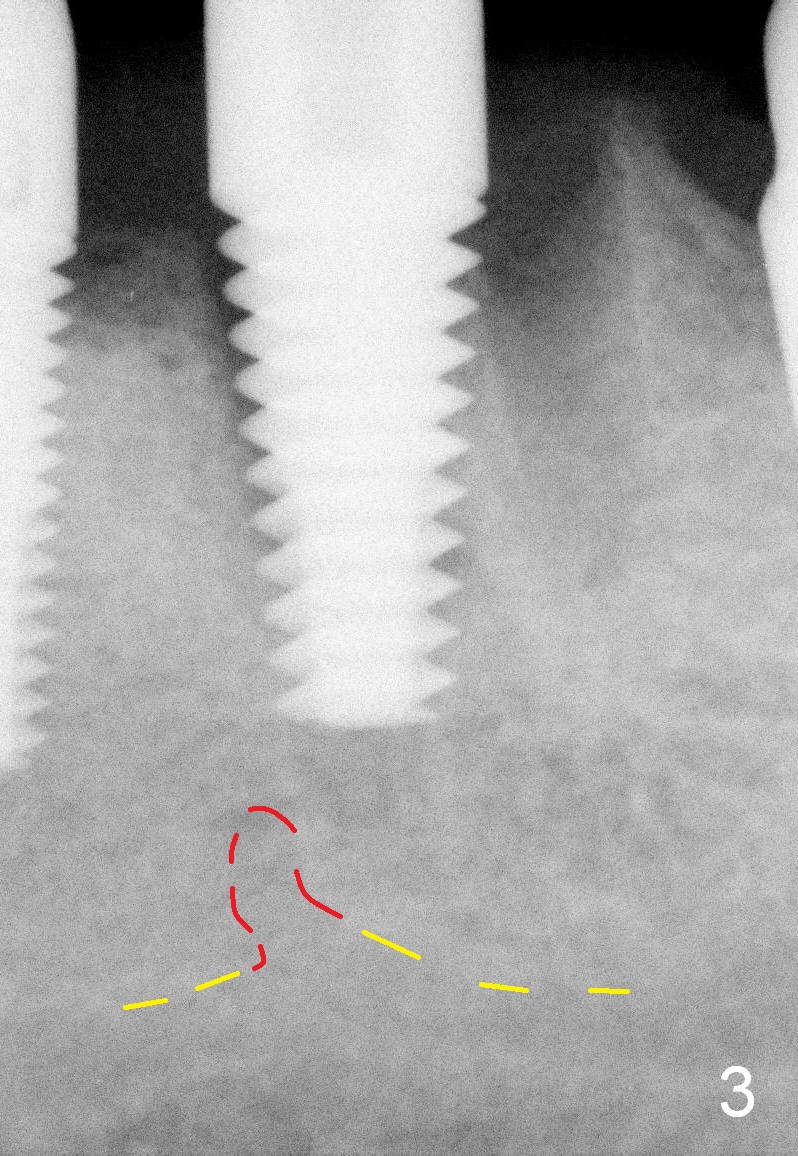

When the infection at the site of #20 is under control, the tooth #19 causes severe pain with mesial periapical radiolucency (Fig.1 *).  Vertical mesial root fracture is confirmed at extraction.  Osteotomy is initiated in the septum (Fig.2 S), but the apical end of the 2 mm pilot drill deviates to the mesial socket.  A Lindamann bur is used to move osteotomy distal, but the implant (6x17 mm) is mainly placed in the mesial socket (Fig.3).  An intraop drawback associated with the deviation is pain control.  The nervous patient questions several times whether it is a good idea to place an implant in the infected site.  Block anesthesia has to be administered.  In fact lack of pain control may be also related to proximity to the Mental Loop (Fig.3 red dashed line).  Fortunately no paresthesia occurs postop, since the implant is somehow placed lingually.

Implant placement in the distal socket is associated with poor restoration.  To place the implant in the septum for this case, it would be the best to find a new entrance point in the septum oblique (Fig.5) after removal of the earlier drill (Fig.4).  Once the entrance point is deep enough, the drill changes its axis and continues osteotomy (Fig.6 thicker red lines).